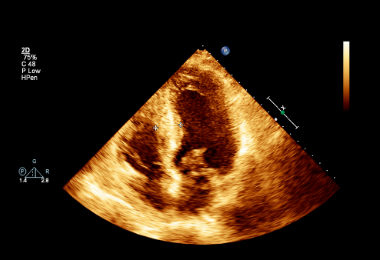

USG serca

Inaczej nazywane ECHO serca. Jest badaniem nieodzownym do podjęcia jakiegokolwiek leczenia kardiologicznego. Dzięki niemu możliwe staje się określenie struktury serca i funkcji zastawek, zaburzeń kurczliwości ściany, przecieków, fal zwrotnych, frakcji wyrzutowej i wielu innych parametrów.